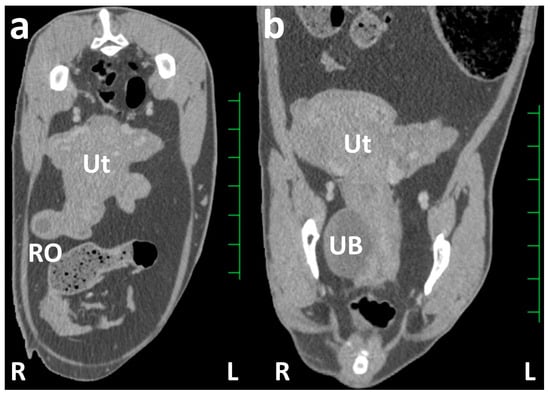

CT: The animal was examined using a slip-ring CT scanner (Pronto SE; Hitachi Co. Ltd., Tokyo, Japan) while positioned in the lateral recumbency on the examination table under anesthesia after intravenous injection of xylazine hydrochloride (0.2 mg/kg; Selactar 2%; Bayer Yakuhin Ltd., Osaka, Japan). The transverse CT images obtained from scanning after intravenous injection of the contrast medium, iopamidol (2.0 mL/kg; Iopamirone 300mg/mL; Bayer Healthcare, Osaka, Japan), displayed a heterogeneously enhanced uterine mass. In this uterine mass, the right uterine horn appeared as a ball-like structure of approximately 5 cm in size at the basal area, and the uterine tube was also enlarged to a thickness of approximately 2 cm (Figure 2a). The lumen of the enlarged right uterine horn and uterine tube was unclear on the CT. The right ovary was approximately 2 cm in size and included a non-enhanced, round, follicle-like structure of a maximum of 10 mm. The left uterine horn was enlarged to a thickness of approximately 3 cm. The structure of the left ovary was not evident on CT because it overlapped with the structure of the uterine horn. On the dorsal CT section of the caudal abdomen, the right uterine horn was thicker than the left (Figure 2b). No morphological or contrast-enhanced abnormalities were observed in other abdominal organs. No lymphadenopathy was evident in the abdominal cavity.

Previous clinical use of CT for diagnosing caprine urogenital diseases has rarely been reported [24,25], despite a few previous reports describing the anatomical evaluation of abdominal CTs in goats [20]. In the CT scans of the caudal abdomen and pelvis, where the narrow cavities are fully crammed with the reproductive tract, the urinary system, colon, and rectum can be identified as separate structures without an overlap in two-dimensional CT sections [20,37]. CT can provide basic transverse cross-sectional images, enabling the reconstruction of every directional plane and a three-dimensional image [20,37]. Reconstructed sagittal CT planes can contribute effectively to evaluating the extent of masses that spread between the abdominal and pelvic cavities and the positional relationship of pathological uterine and ovarian structures against the peripheral organs [25,38]. Detecting the systemic formation of metastatic foci and lymphadenomegaly during whole-body scanning using CT can lead to diagnostic suggestions for neoplastic lesions [24,25]. The CTs of reproductive tract lesions can be evaluated quantitatively by measuring lesion size and Hounsfield units [37]. In the present case, the CT-based measurement of ovarian follicle size within the right ovary helped diagnose a follicular cyst based on the ultrasonographic criteria of follicular cysts [3,7,11,21]. These cysts were >10 mm in size [3,7,11,21], compared with 8–9 mm of the maximum size of a follicle formed within the ovary in the estrous cycle of female goats [11,18]. Contrast techniques for radiographic examination are applicable to CT scanning [25,38,39]; these techniques include excretory urography, retrograde cystography [38], hysterography, identifying the pathological enlargements of the affected uterus and fertile states [14,16], and vaginography, helping in diagnosing ectopic ureters and urethrovaginal and rectovaginal fistulas [15,39]. The intravenous injection of contrast medium during CT scanning can provide significant evidence of contrast enhancement, such as the difference in contrast-enhanced density within the lesions and the time required for contrast enhancement [24]. Contrast enhancement and fluid retention within the uterine lumen are significant CT features that differentiate between neoplastic and non-neoplastic uterine diseases [25]. In the present case, contrast CT revealed that the thickened uterine walls were occupied predominantly by a fluid retention area within the enlarged uterine structure.

Figure 2. Transverse (a) and dorsal (b) contrast computed tomography images of the caudal abdomen. (a) The right uterine horn is shown as an enlarged, round structure, larger than that of the left uterine horn. The homogenously contrast-enhanced structure represents the enlarged uterus (Ut), wherein the uterine lumen is unclear. The contrast-enhanced ball-like structure of the right ovary (RO) includes a round cystic structure with weak contrast enhancement. (b) The uterus (Ut) is represented as the enlarged uterine cervix running along the urinary bladder (UB) within the pelvic cavity, and the uterine horns extend to the location approximately 4 cm cranially compared with the pelvis. Scale = 25 mm.